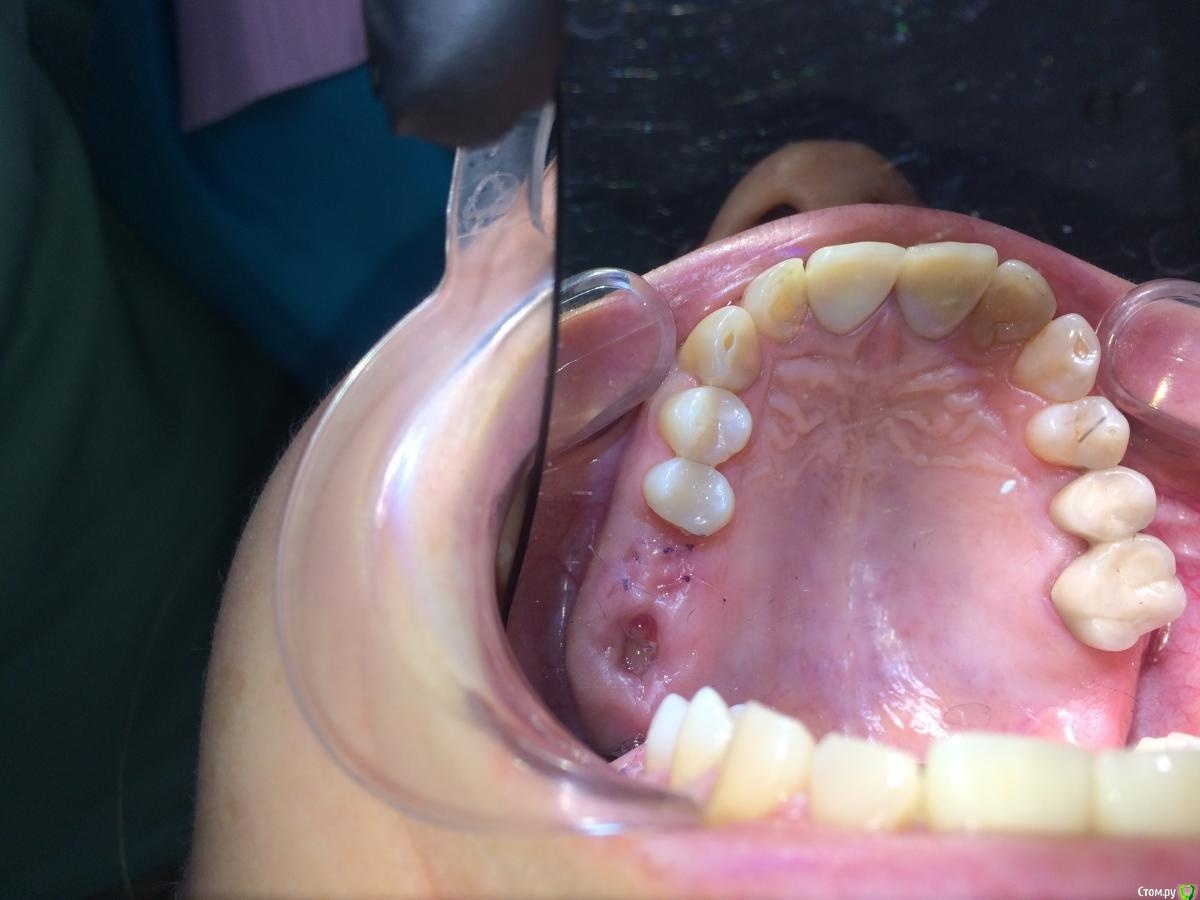

Doctor Vlad Опубликовано 14 апреля, 2020 Поделиться Опубликовано 14 апреля, 2020 Привет, друзья! Вот такая ситуация после удаления. В момент удаления сообщения не было, но виднелась слизистая пазухи. Аккуратно цистэктомия проведена. Заложил губкой и ушил. На осмотре чз неделю уже заметил отклонение в заживлении. Спустя пару недель сам назначил проверить и вот такое обнаружил. Никак не беспокоит, сообщения нет. Слизистая как клапан вдавливается внутрь. 27 тоже удалять, там тоже дефект большой кости, и синус близко. сразу не стал его трогать.Планирую иссечь и с неба лоскут перетянуть. 27 наверно отдельным этапом чтобы дыру не увеличить. нужно ли со стороны синуса вмешательство? или достаточно со стороны рта все ушить?кт поищутут наглядно https://www.dropbox.com/s/1lgvixk2qpqi8gp/WhatsApp%20Video%202020-04-14%20at%2010.15.44.mp4?dl=0 Ссылка на комментарий

Doctor Vlad Опубликовано 14 апреля, 2020 Автор Поделиться Опубликовано 14 апреля, 2020 Почему клапан то? В какую-то сторону пропускает разве? ИМХО,если планируете дальнейшую работу тут - дайте минимум 2 месяца. Потом кточень похоже на клапан... обычно это просто свищ очень тонкий... если смотрели видео с дропбокса выше, вроде не пропускало но ходит высоко, я могу прям в глубину задвинуть ее и эта пипка возвращается. прошло где-то 2 месяца. у меня и был план выждать чтобы дать возможность лунке зажить. боюсь время потерял из-за пазухи( не по разрасталось бы там чего).а 27 трогать не стал, чтоб 2 соустья не сделать. там на кт видно дефект в фуркации и не видно слой костной ткани Ссылка на комментарий

Irouil Опубликовано 14 апреля, 2020 Поделиться Опубликовано 14 апреля, 2020 Клапан - это когда в одну сторону пускает, а в другую нет. А у Вас, на мой взгляд, просто дефект альвеолярного гребня с формированием герметичного мягкотканного рубца. Со временем он должен созреть и стать плотнее, что исключит риски для состояния здоровья пациента и, если бы планировалась только санация, то на этом можно было бы остановиться. Ну а для реконструкции гребня надо, конечно, свежее КТ. Ссылка на комментарий

Doctor Vlad Опубликовано 14 апреля, 2020 Автор Поделиться Опубликовано 14 апреля, 2020 Клапан - это когда в одну сторону пускает, а в другую нет. А у Вас, на мой взгляд, просто дефект альвеолярного гребня с формированием герметичного мягкотканного рубца. Со временем он должен созреть и стать плотнее, что исключит риски для состояния здоровья пациента и, если бы планировалась только санация, то на этом можно было бы остановиться. Ну а для реконструкции гребня надо, конечно, свежее КТ. Похоже на утолщенную слизистую синуса. с клапаном разобрался) Ссылка на комментарий